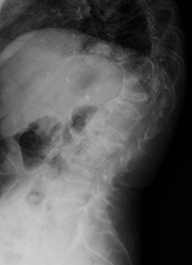

因:“腰椎骨折椎体成形术后2天”入院

患者因“脑卒中后遗症”在我中心康复治疗,于4月27日行走时滑倒腰部跌伤,当时即感疼痛,活动受限,到当地医院就诊,经CT等检查后,诊断为L3骨折,予卧床休息、口服活血化瘀及镇痛等对症治疗,患者自觉症状无改善,于6月03日在上级医院行椎体成形手术,2014年6月04日再次转入我中心继续康复治疗。患者入院时腰背部疼痛明显改善,并可下床活动。

神清,精神可,轮椅推入病房,精神略显紧张,发育正常,营养中等,呼吸平稳,查体合作,言语清晰,对答切题。全身皮肤粘膜无黄染,无皮疹、无淤斑、淤点,毛发分布正常,皮温正常、皮肤弹性正常,无肝掌。浅表淋巴结未及肿大。头颅大小正常,无畸形,眼睑无水肿,结膜无充血,眼球正常,无运动障碍,巩膜无黄染,角膜正常,双侧瞳孔等大等圆7.5px,对光反射正常。左侧鼻唇沟浅,左侧口角下垂,左侧额纹消失,耳廓正常,外耳道无脓性分泌物,乳突无压痛,双侧听力正常。鼻外形正常,鼻道畅,鼻中隔无偏曲,鼻旁窦无压痛。口唇红润无绀,口腔粘膜正常,舌正常,伸舌居中,牙龈无肿胀出血,咽无充血,双侧扁桃体未见肿大,声音正常。颈软,无抵抗,脑膜刺激征阴性,气管居中,颈静脉无充盈,双侧甲状腺未及肿大,无压痛。胸廓无明显畸形,乳头对称,双侧呼吸运动对称,语颤相等,叩诊清音,双肺呼吸音粗,未及明显干湿啰音。心前区未见异常隆起,心尖搏动位于左第5肋锁骨中线内12.5px,未及震颤,心相对浊音界正常。心率80次/分,律齐,各瓣膜听诊区未闻及病理性杂音。未及水冲脉、股动脉枪击音。腹平,未见腹壁静脉曲张,未见肠型蠕动波,腹软,无压痛、反跳痛,肝脾肋下未及,肾未触及,全腹未触及包块,肝肾区无叩痛,移动性浊音阴性,肠鸣音正常,5次/分。脊柱胸腰段后凸畸形,活动度轻度受限,棘突无明显叩痛,双下肢无水肿。四肢肌力正常,关节无畸形。双下肢感觉正常。

入院诊断:(1)腰椎骨折术后